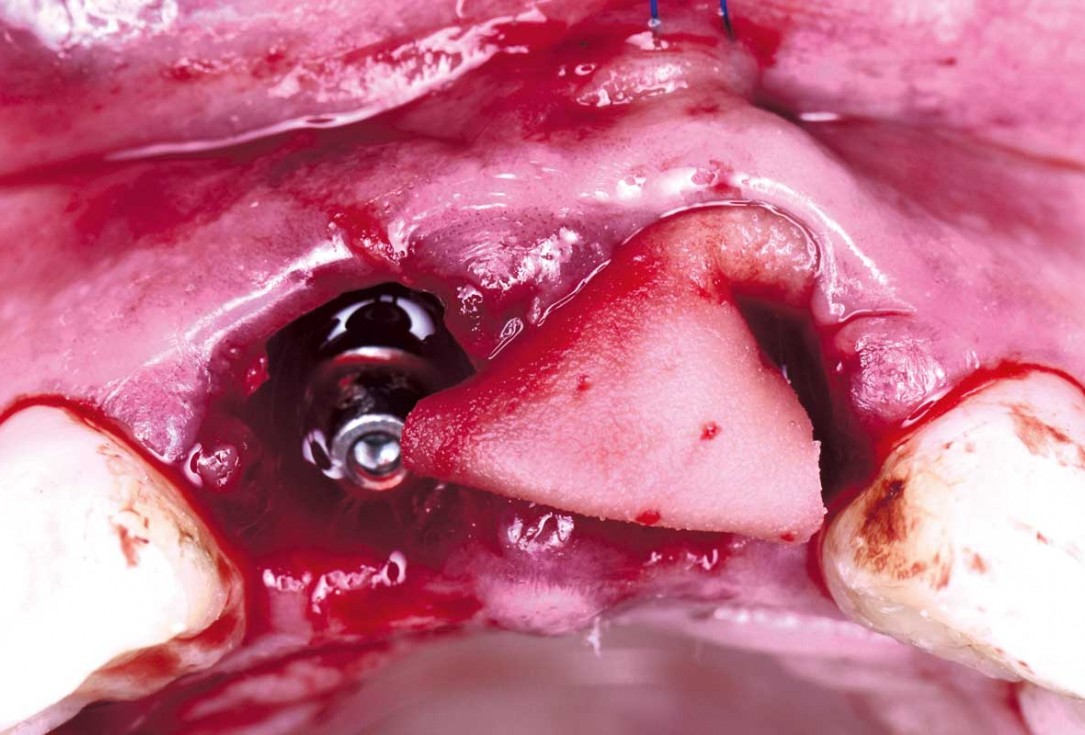

06/22 - To improve the soft tissues, two folded mucoderm® are placedcerabone® and mucoderm® for immediate implantation in the aesthetic area - Dr. D. Robles